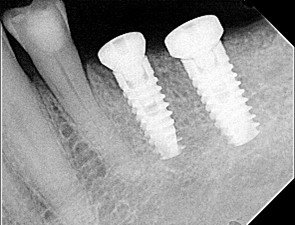

After a thorough dental and medical evaluation, including a complete set of x-rays and CBCT, a plan was developed for him. This included the removal of all broken and infected teeth, rebuilding the lower anterior teeth to improve his anterior occlusion, restoring the teeth that could be saved, and placing implants in the future edentulous sites of the lower arch. You can see on the x-rays and CBCT these areas.

At the eighth-month appointment, implants were placed in the #19, 20, 29, and 31 sites because the bone filled in nicely. Insertion torque was over 40 NCM for all implants. Healing screws were placed, and then we waited for osseointegration of the implants.